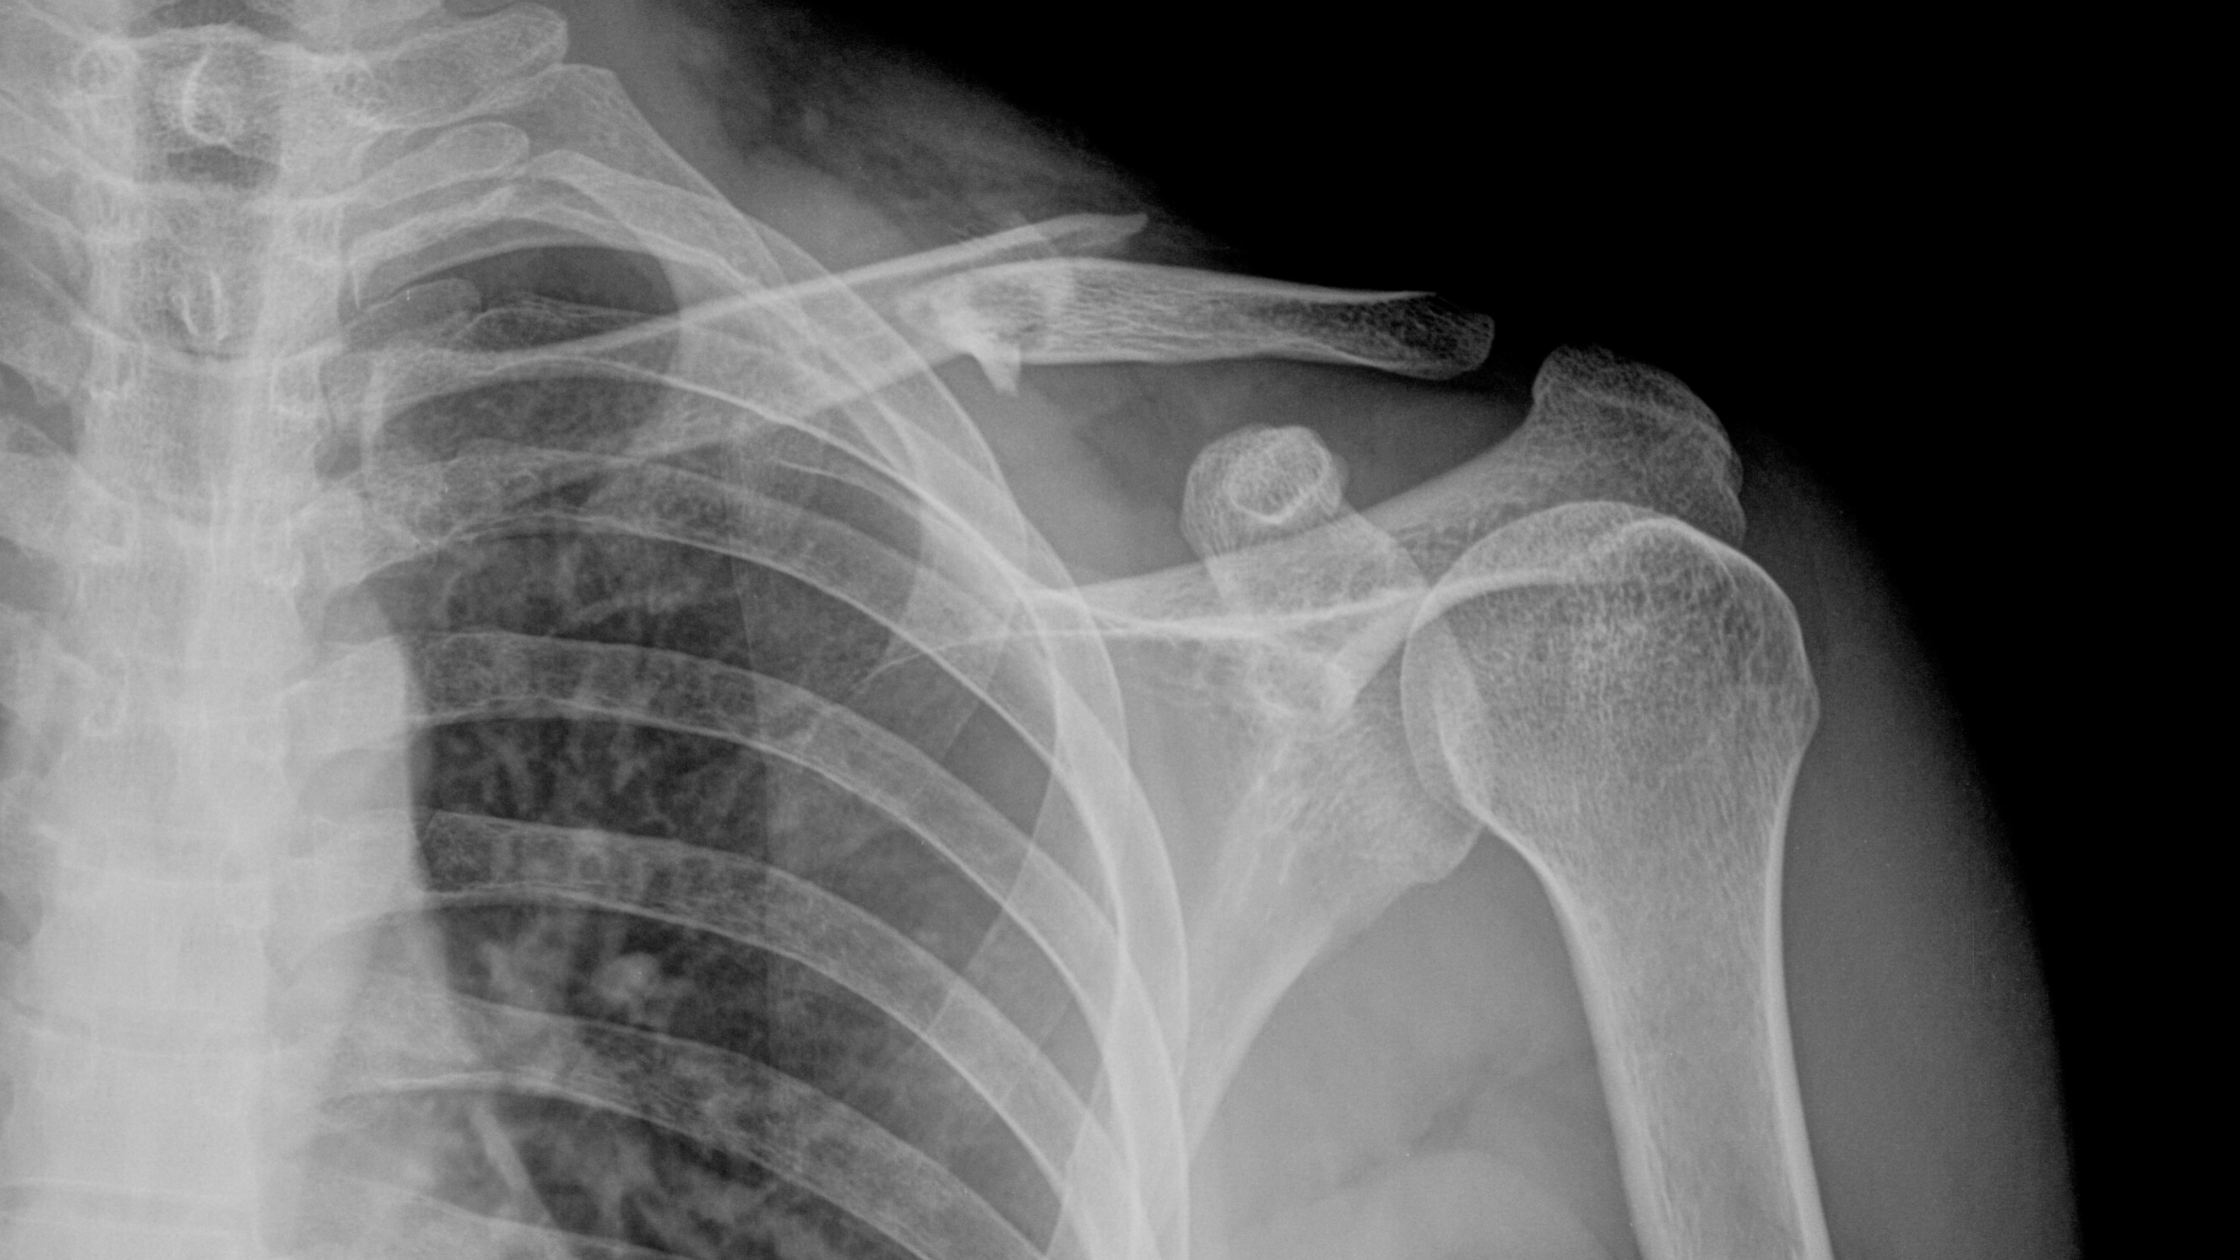

Clavicular fractures are nasty and bio-mechanically they cause us lots of problems. The clavicle is an attachment point for several muscles namely sterno- cl…